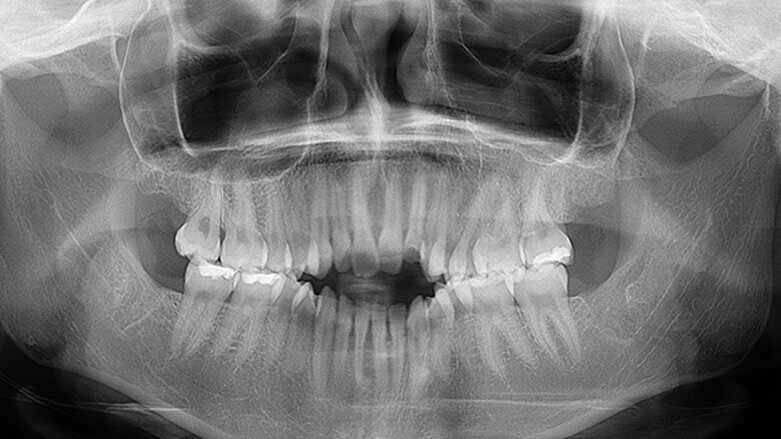

Ilustrační fotografie